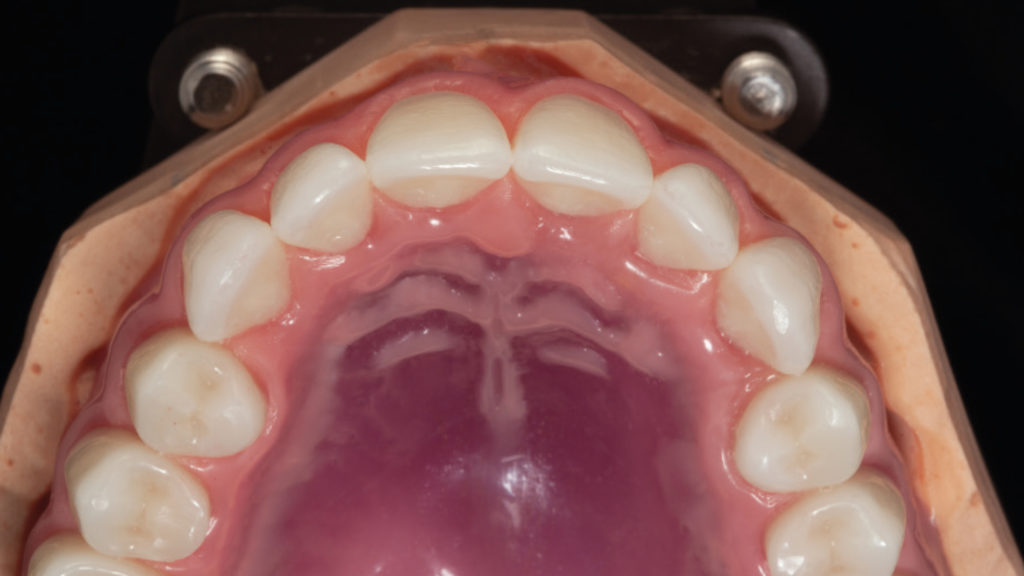

Im Rahmen der Fertigung der beiden Prothesen wurde also beschlossen, um Zahn 46 herumzuarbeiten. Die Patientin wünschte sich eine natürlich wirkende Neuversorgung, die ihr durch einen guten Halt Sicherheit beim Kauen und Sprechen bot. Sie entschied sich nach eingehender Beratung für eine totalprothetische Neuanfertigung. Der Konfektionszahn Vitapan Excell wurde in der passenden Zahnform gewählt, um eine natürliche Wirkung und eine Aufstellung nach dem ästhetischen Regelwerk zu gewährleisten. Im Seitenzahnbereich kam der Vitapan Lingoform zum Einsatz. Als erste Arbeitsgrundlage wurden anatomische Situationsabformungen mit Alginat genommen, um im Labor individuelle Löffel herzustellen. In einer zweiten Sitzung wurden mit diesen mukodynamische Abformungen genommen (Abb. 2). Die erste Abformung erfolgte mit Heavy Body, die zweite Feinabformung mit Light Body A-Silikon. Nach der Meistermodellherstellung wurden auf dieser Grundlage Bissregistrate mit Wachswällen für die Kieferrelationsbestimmung hergestellt. Die räumliche Anordnung der Kiefer zueinander konnte mit den intraoral entsprechend verschlüsselten Registraten in den Artikulator übertragen werden (Abb. 3). Nach der Modellanalyse wurde mit der patientengerechten Aufstellung in Wachs begonnen (Abb. 4).